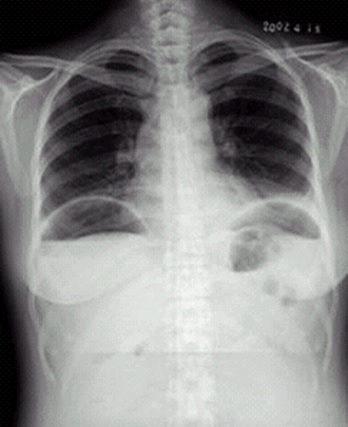

04卷-4.病史:女性,42歲,腹痛1天,進(jìn)行性加重。診斷(本題滿分2.00分)

本題答案:D

題目解析:【該題針對“X線-消化道穿孔”知識點進(jìn)行考核】